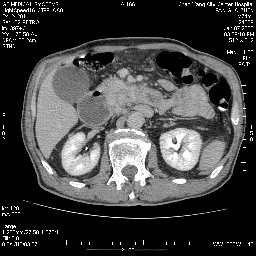

双肾多发小囊肿;左肾积水。

今日手术结果:胰腺钩突癌侵犯十二直肠,腹腔淋巴结转移.

胰腺钩突癌侵犯十二直肠,腹腔淋巴结转移.

十二指肠降段扩张,水平段狭窄成鼠尾状,肠壁明显增厚,胰腺勾突增大成不均匀强化,,胆囊增大,十二指肠水平段腺癌侵犯胰腺